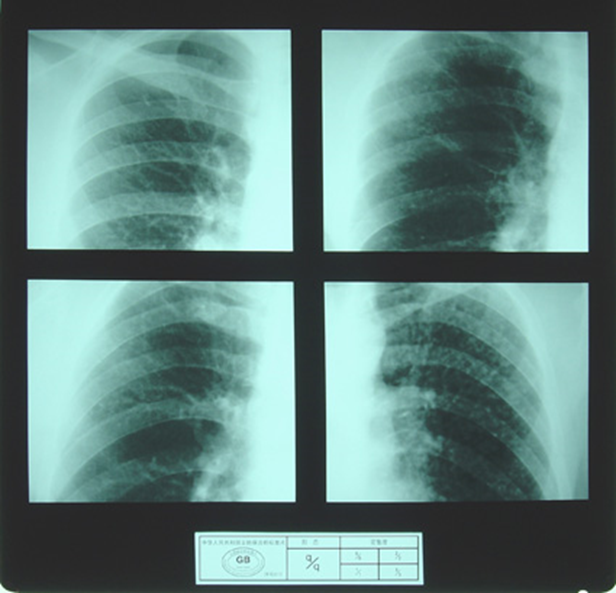

(2)X射线胸片表现:矽肺X射线胸片影像是肺组织矽肺病理形态在X射线胸片的反映,是“形”和“影”的关系,与肺内粉尘蓄积、肺组织纤维化的病变程度有一定相关关系,但由于多种原因的影响,并非完全一致。这种X射线胸片改变表现为X射线通过病变组织和正常组织对X射线吸收率的变化,呈现发“白”的圆形或不规则形小阴影,作为矽肺诊断依据。X射线胸片上其他影像,如肺门变化、肺气肿、肺纹理和胸膜变化,对矽肺诊断也有参考价值。在X射线胸片上,肺野内直径或宽度不超过10mm的阴影。小阴影按其形成分为圆形和不规则形两类。

2)不规则形小阴影:多为接触游离二氧化硅含量较低的粉尘所致,病理基础主要是肺间质纤维化。表现为粗细、长短、形态不一的致密阴影。阴影之间可互不相连,或杂乱无章的交织在一起,呈网状或蜂窝状;致密度多持久不变或缓慢增高。按其宽度可分为s(<1.5mm)、t(1.5~3.0mm)、u(3.0~10mm)三种类型。早期也多见于两肺中下区,弥漫分布,随病情进展而逐渐波及肺上区。

不规则形小阴影(s类小阴影)

不规则形小阴影(t类小阴影)

不规则形小阴影(u类小阴影)

3)大阴影:在X射线胸片上,肺野内直径或宽度超过10mm的阴影,为晚期矽肺的重要X射线表现,形状有长条形、圆形、椭圆形、或不规则形,病理基础是团块状纤维化。大阴影的发展可由圆形小阴影增多、聚集,或不规则小阴影增粗、靠拢、重叠形成;多在两肺上区出现,逐渐融合成边缘较清楚、密度均匀一致的大阴影,常对称,形态多样,呈八字形等,也有先在一侧出现;大阴影周围一般有肺气肿带的X射线表现。

大阴影

2)尘肺贰期:有下列表现之一者:

a) 有总体密集度2级的小阴影,分布范围超过4个肺区;

b)有总体密集度3级的小阴影,分布范围达到4个肺区。

3)尘肺叁期:有下列表现之一者:

a) 有大阴影出现,其长径不小于20mm,短径不小于10mm;

b)有总体密集度为3级的小阴影,分布范围超过4个肺区并有小阴影聚集;

c) 有总体密集度为3级的小阴影,分布范围超过4个肺区并有大阴影。

尘肺贰期

尘肺贰期

尘肺贰期

尘肺叁期

尘肺叁期

尘肺叁期